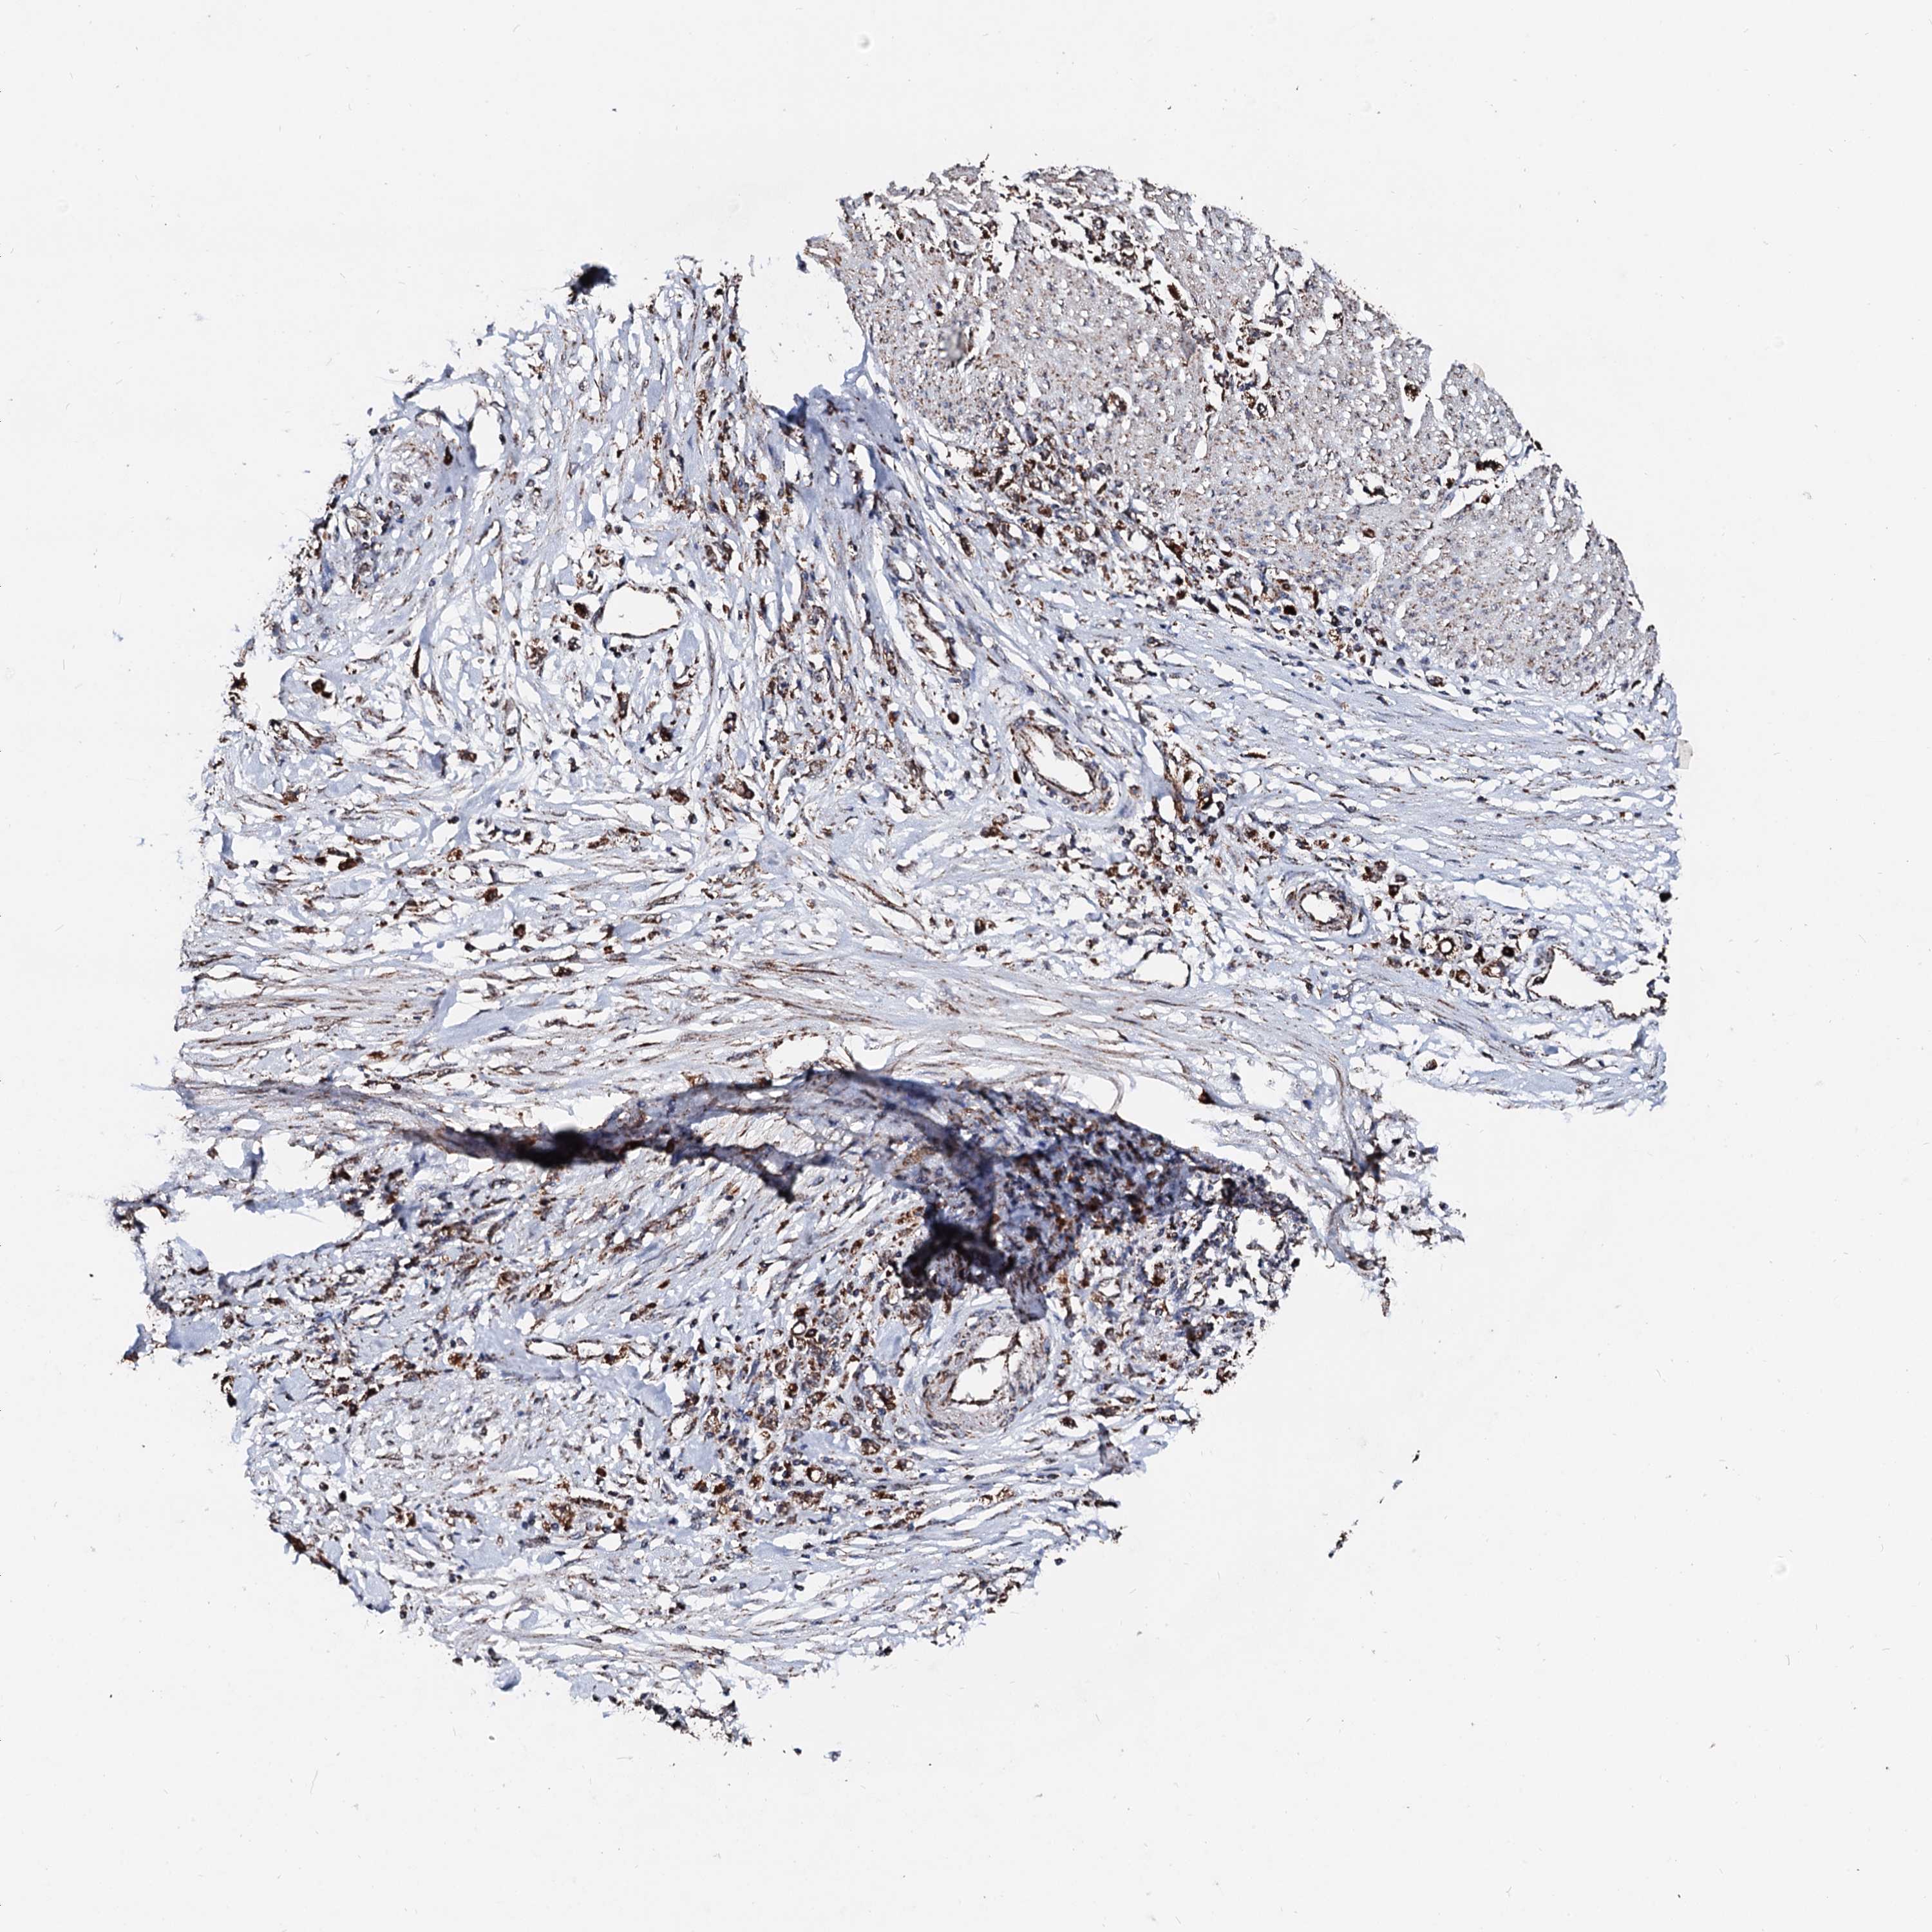

STOMACH CANCER - Protein expressioni

A mouse-over function shows sample information and annotation data. Click on an image to view it in a full screen mode. Samples can be filtered based on level of antibody staining by selecting one or several of the following categories: high, medium, low and not detected. The assay and annotation is described here.

Note that samples used for immunohistochemistry by the Human Protein Atlas do not correspond to samples in the TCGA dataset.

Antibody stainingi

Antibody staining in the annotated cell types in the current human tissue is reported as not detected, low, medium, or high, based on conventional immunohistochemistry profiling in selected tissues. This score is based on the combination of the staining intensity and fraction of stained cells.

Each image is clickable and will lead to virtual microscopy that enables deeper exploration of all samples and also displays staining intensity scores, fraction scores and subcellular localization as well as patient and tissue information for each sample.

Antibody HPA039875

Staining

High

Medium

Low

Not detected

Intensity

Strong

Moderate

Weak

Negative

Quantity

>75%

75%-25%

<25%

None

Location

Nuclear

Cytoplasmic/membranous

Cytoplasmic/membranous,nuclear

Adenocarcinoma, NOS